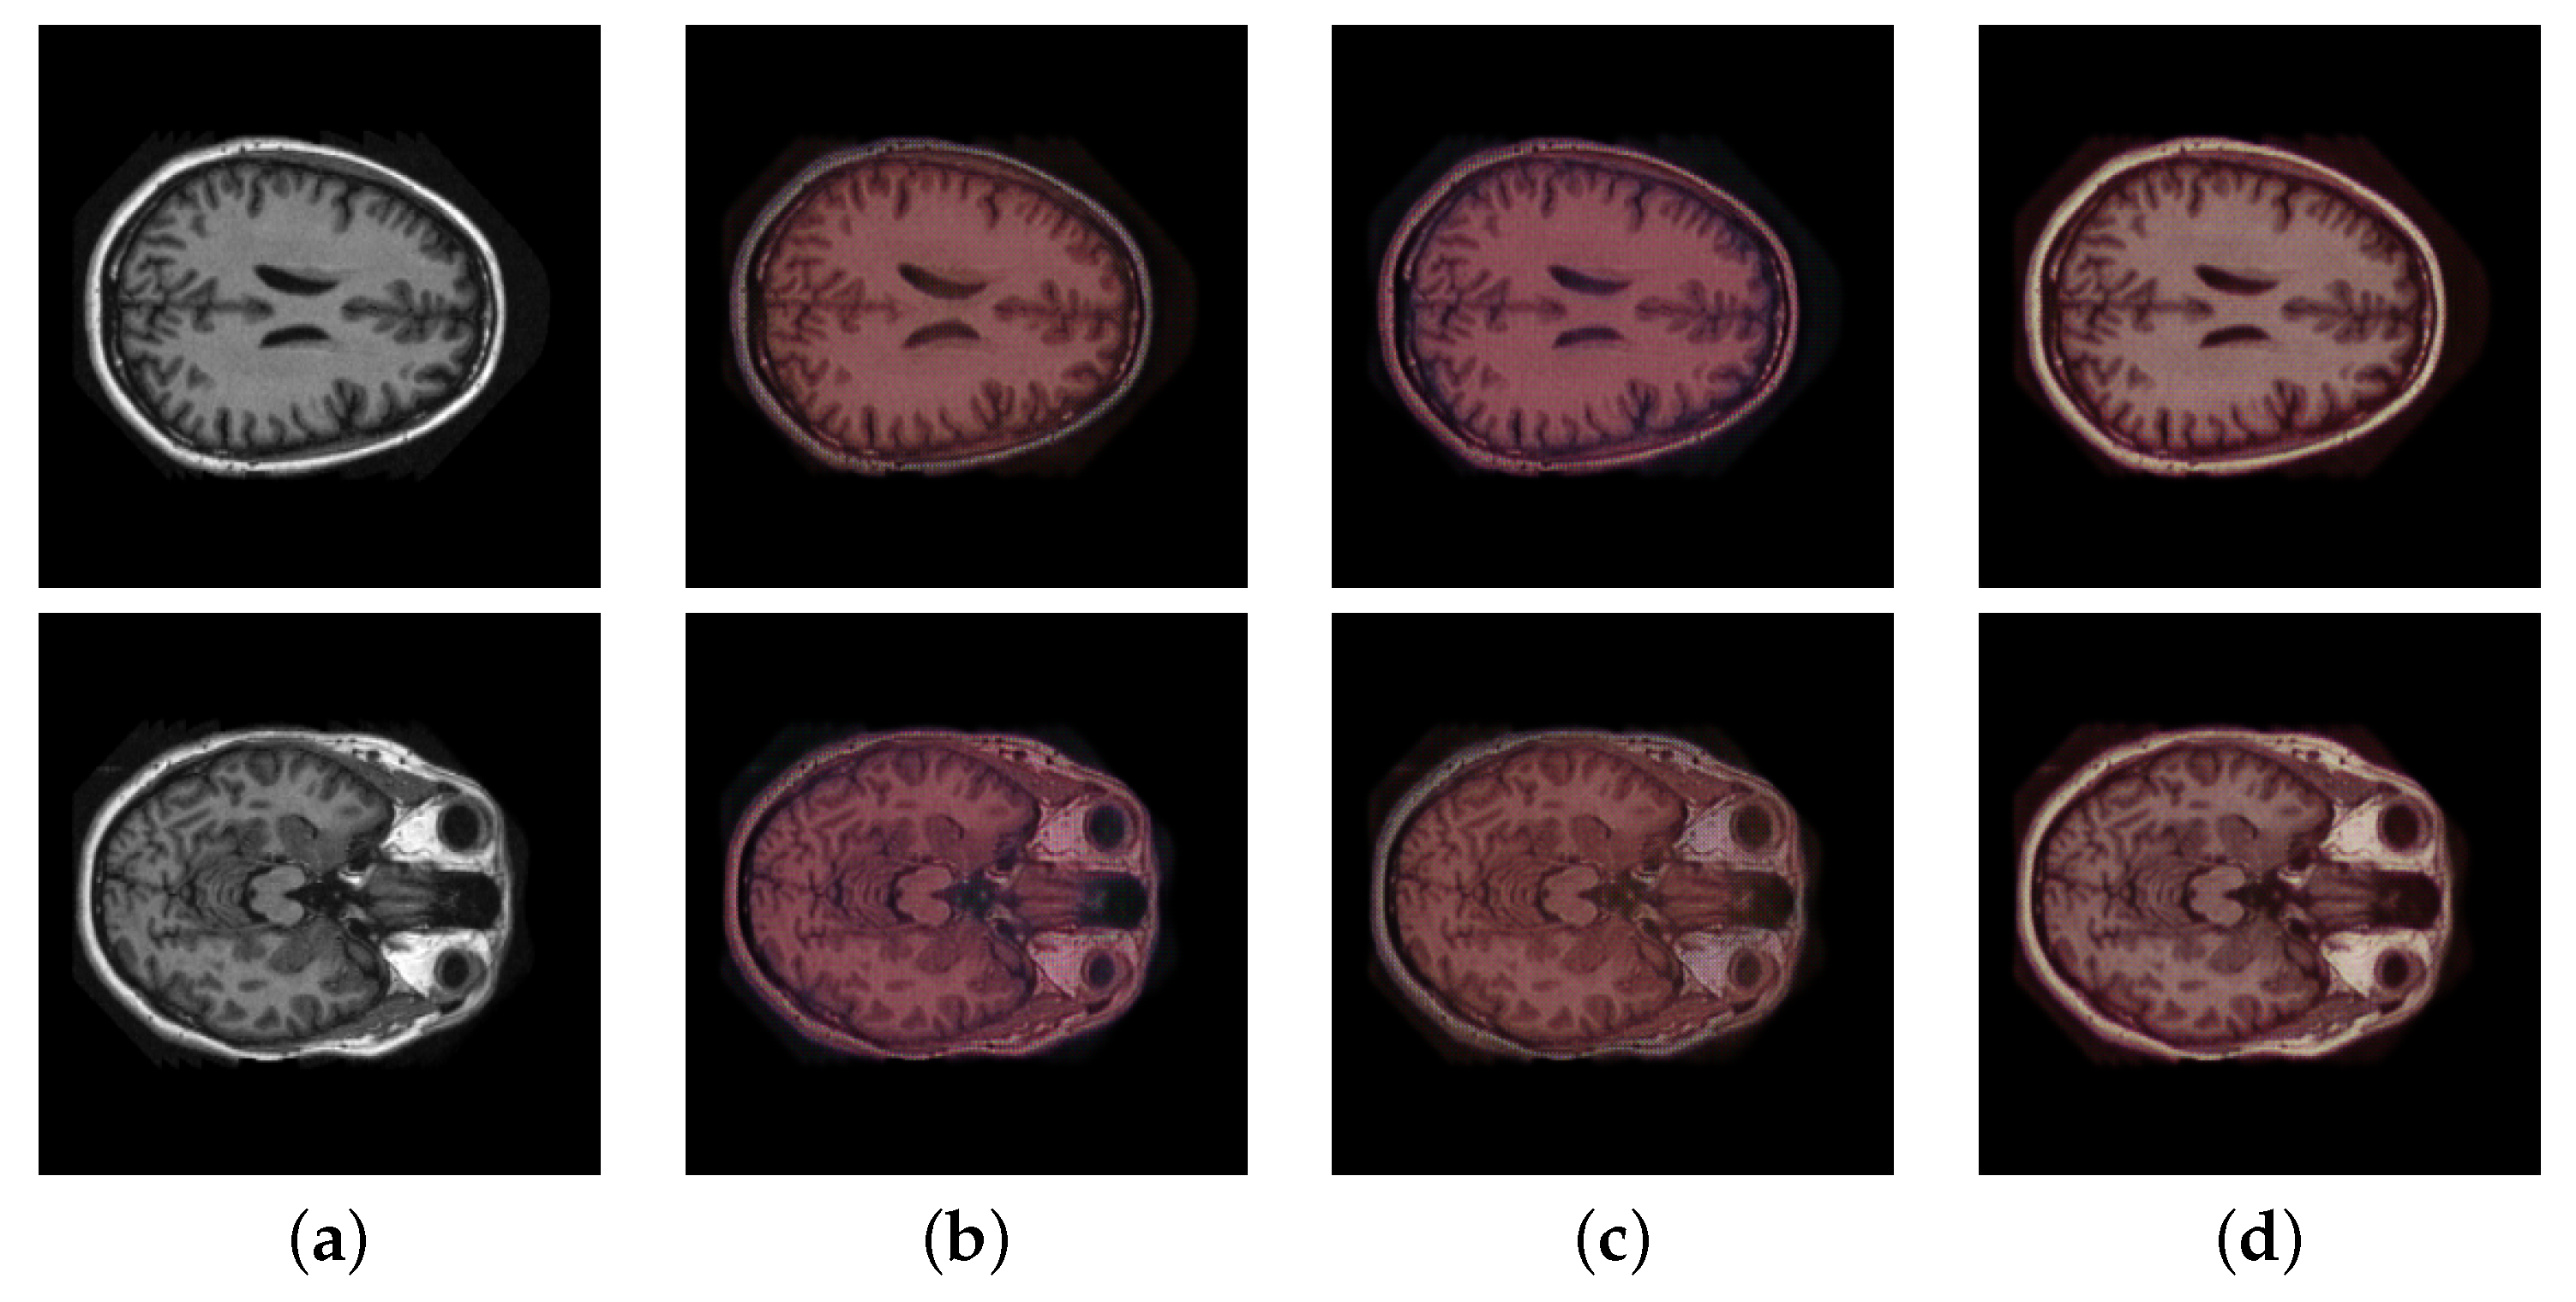

3.1. Ablations Analysis

3.1.1. Effectiveness of Edge Loss

3.1.2. Performance of Semantic Module

3.1.3. The Multi-Modal Discriminator

| w/o edge loss | 0.745 | 20.735 | 112.15 |

| w edge loss | 0.757 | 21.010 | 110.32 |

| w/o segmentation module | 0.757 | 21.010 | 105.23 |

| w segmentation module | 0.857 | 29.698 | 84.81 |